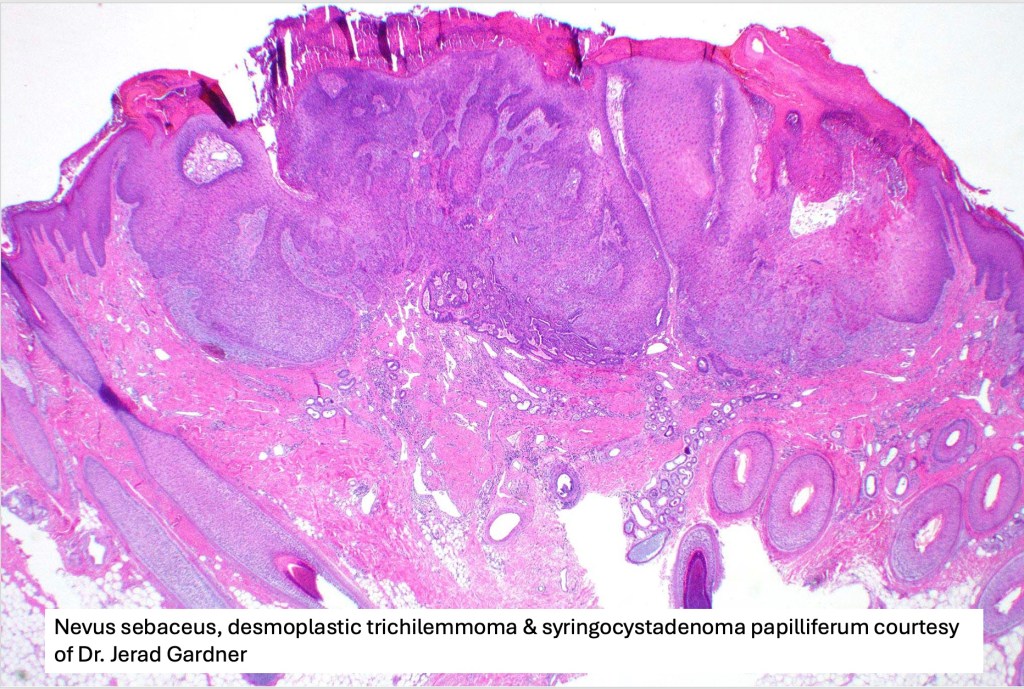

•A common tumor in a background of nevus sebaceus

•Scanning magnification shows an exophytic tumor or an epidermal invagination enclosing epithelial covered papillae with a fibrovascular core

•Glands are present at the base of the lesion

•At the edges, the squamous epithelium is in continuity with the glandular one

•The epithelium consists of outer myoepithelial cells supporting an inner layer of columnar cells with abundant eosinophilic cytoplasm showing decapitation secretion

•Dense plasma cell infiltrate